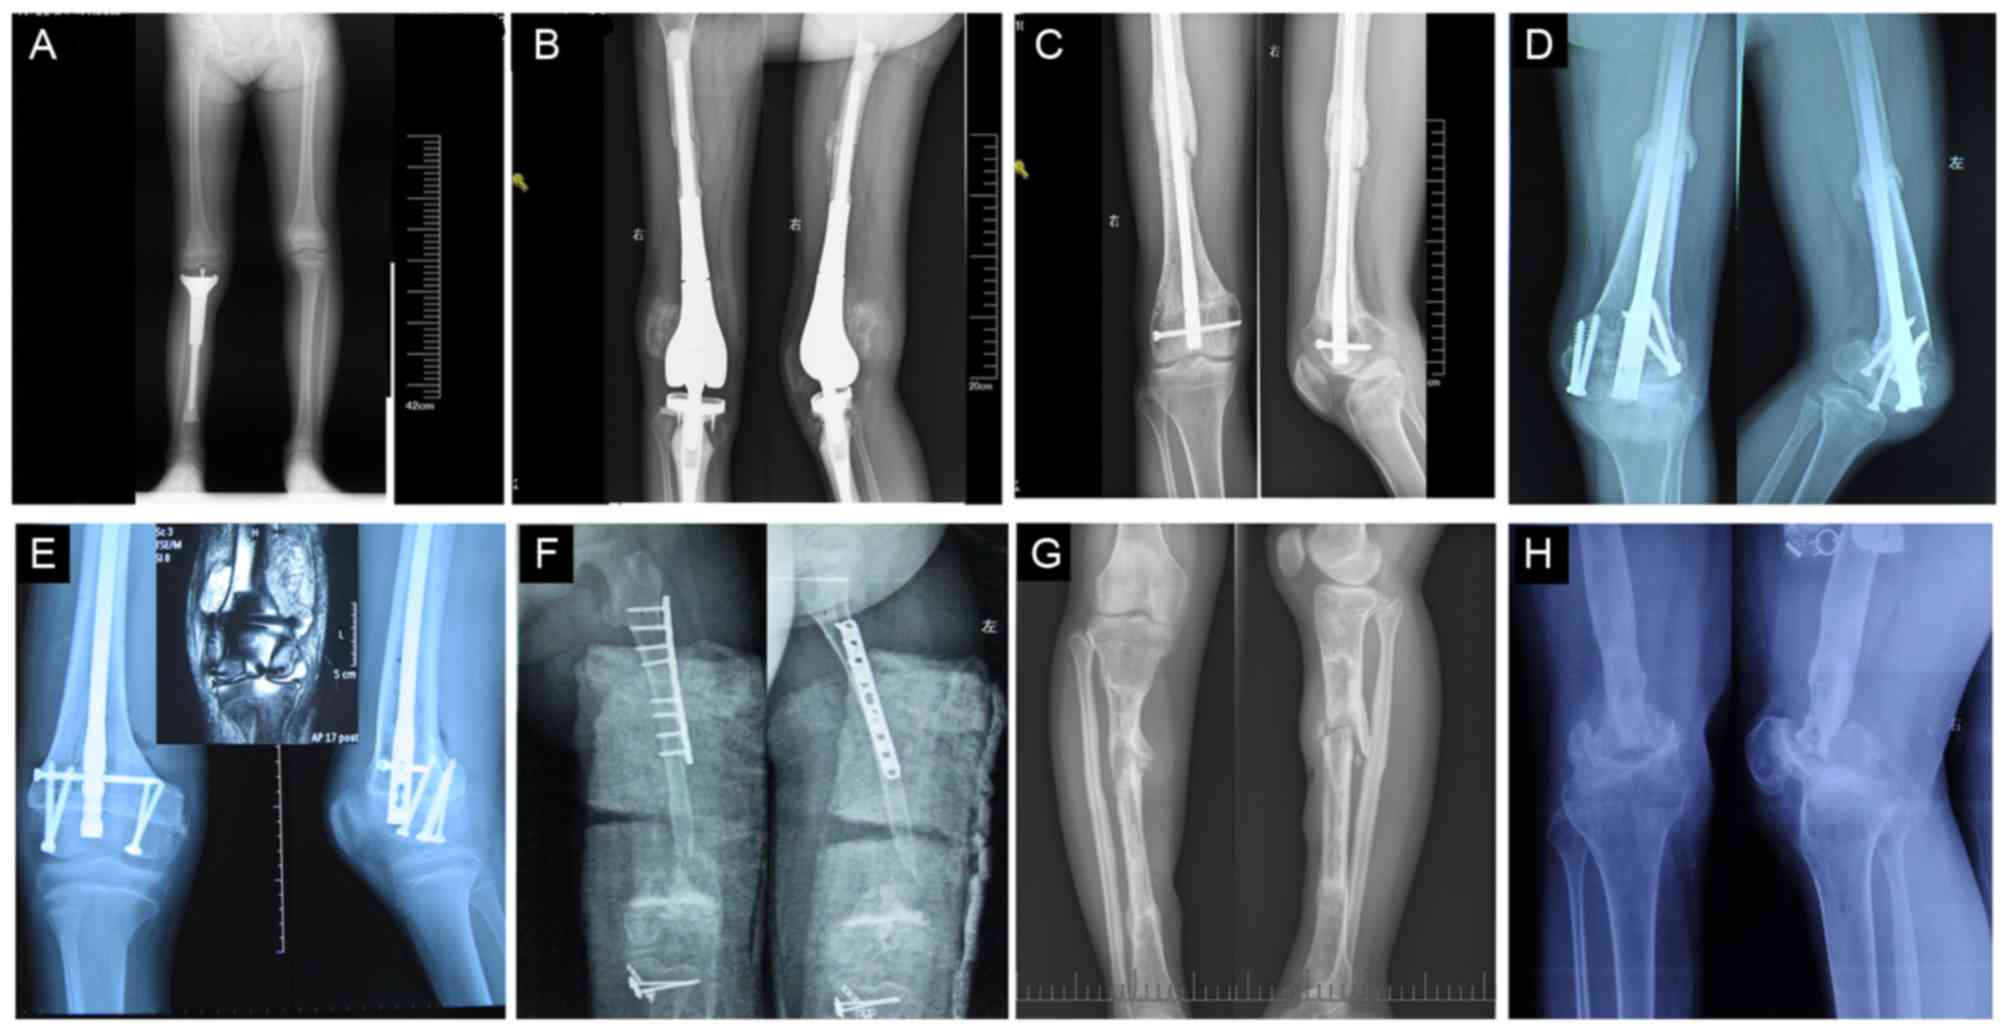

Ol Type 3 Severe

Brittle Bone Disease Osteogenesis Imperfecta